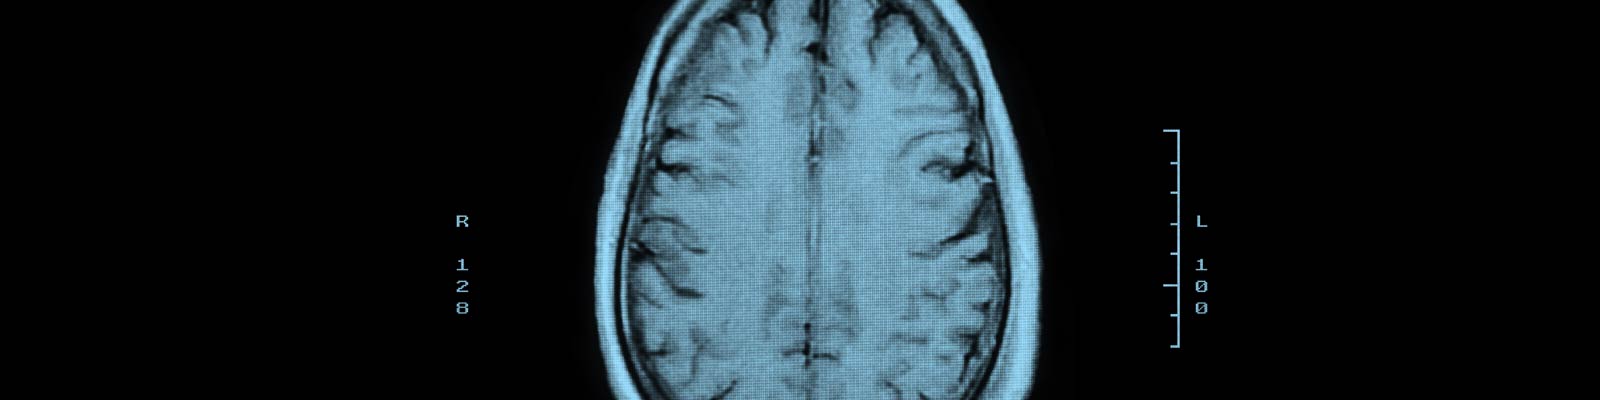

La lesión cerebral, conocida por algunos como traumatismo craneoencefálico o TCE, es una lesión catastrófica que a menudo resulta en daño permanente o muerte, sobre todo si no se trata adecuadamente y de forma inmediata. Una lesión cerebral puede ser el resultado de un accidente en coche, un resbalón y caída, un acto violento, un asalto u otros ataques, y accidentes deportivos o de trabajo.

Las víctimas de lesiones en la cabeza pueden padecer trastornos en los músculos, el habla, la visión, el gusto o el oído dependiendo del área del cerebro o de la cabeza que está lesionada, y del alcance de esas lesiones. También es común que las víctimas experimenten cambios a corto o largo plazo en su memoria, comportamiento y personalidad. Una lesión cerebral puede afectar tanto el estado físico de la víctima, que la inhabilite para trabajar y mantener a su familia. Además, puede causar cambios de humor extremos, terribles dolores de cabeza y sufrimiento emocional. Las víctimas de traumatismo craneoencefálico pueden pedir una indemnización por daños y perjuicios que incluya el pago de los gastos médicos, los salarios perdidos, la pérdida de ingresos futuros, la pérdida de medios de vida, la hospitalización, las cirugías, la rehabilitación, las lesiones permanentes, la discapacidad, el dolor y sufrimiento, y angustia emocional.